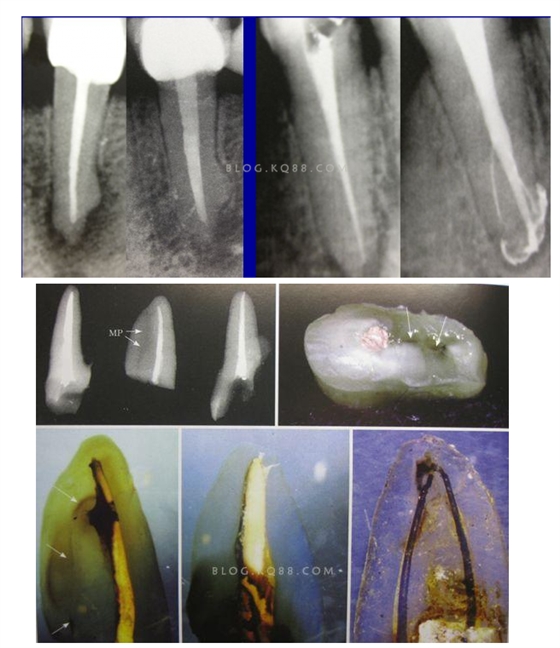

2相信有更多的根管存在 相信根管的數(shù)目比我們想象的多,根管系統(tǒng)的復(fù)雜程度比我們想象的見到的要更復(fù)雜,我們只有用盡所有努力和辦法才可能達到預(yù)期目標(biāo),對于上 牙合 6的MB2來說過去是偶爾有,現(xiàn)在是偶爾沒有,各種文獻報道的比例也不一致,我在培訓(xùn)班醫(yī)生帶來的離體牙中幾乎沒有見到?jīng)]有的,臨床中也是一樣。對于尋找的方法來說,我覺得相信有才是最重要的,首先相信一定有就會想各種辦法,找到的幾率就會更多。如果有條件在顯微鏡和超聲的配合下效率會更高。

3、感染控制決定成敗 根管治療中感染控制的徹底程度直接決定根管治療的成功率,對主根管、牙本質(zhì)小管、側(cè)支根管的控制同等重要;完善根管治療后的患牙失敗主要原因是根管系統(tǒng)的頑固的感染或根尖周頑固的根管外細菌感染,當(dāng)然也有可能是非細菌性因素,但根管內(nèi)的感染占主要原因。在高效率的機械預(yù)備根管時,一定要用專用的側(cè)方開口針頭的注射器大量多次的沖洗根管,次氯酸鈉要加熱后使用,并及時補充新鮮的液體到根管系統(tǒng),EDTA液體的使用可以很好去除根管預(yù)備中產(chǎn)生的玷污層,1%的CHX液體可以在30秒內(nèi)殺滅糞腸球菌,并且有延緩作用,是優(yōu)秀的終末沖洗液。超聲蕩洗清理根管的效果要優(yōu)于手工沖洗。很多醫(yī)生考慮次氯酸鈉的濃度,其實次氯酸鈉沖洗液的濃度并不重要,重要的是沖洗的時間和次數(shù),更換新鮮液體的頻率和液體是否加熱。

4、敢于否定自己 有些病例看上去似乎是完美的,但是患者就是感覺有明顯的不適感,就應(yīng)該考慮是否有未處理的根管內(nèi)感染區(qū)域,分析是根管、峽部、分支、縫隙等原因后就要及時的采取措施,失敗病例的處理方法選擇非手術(shù)再治療還是手術(shù)再治療,一般首選非手術(shù)再治療,但要評估再治療的預(yù)期結(jié)果,如果非手術(shù)再治療的對患牙的創(chuàng)傷太大或預(yù)期效果不確定就考慮手術(shù)再治療,全面考慮分析后決定方法。要及時的決定下一步的處理方法。長期的反復(fù)的復(fù)診觀察是沒有意義的,最后的結(jié)果是流失患者。

5、預(yù)備到多少號結(jié)束根管預(yù)備理想的情況應(yīng)該預(yù)備到多大錐度,多少號,預(yù)備后根管空間是金字塔還是埃菲爾鐵塔。專家經(jīng)過離體牙根尖切片研究發(fā)現(xiàn)根尖狹窄部遠比想象的要大,如果根管預(yù)備太小就會殘留感染物,根管的部分空間就不會預(yù)備到,殘留的感染物就會造成治療效果達不到預(yù)期目標(biāo)。只有做到了充分的預(yù)備,盡可能的多沖洗才會有好的結(jié)果。